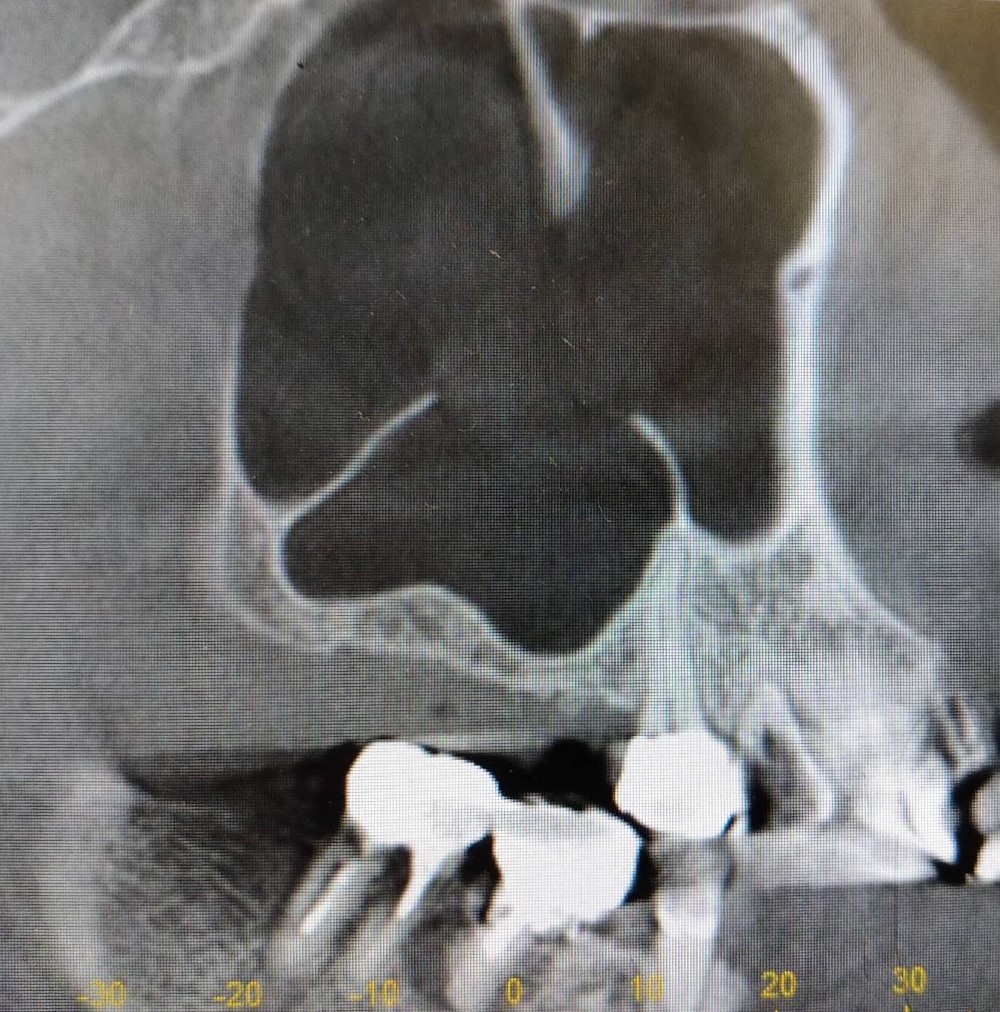

上顎洞底挙上術を併用したインプラント埋入の症例紹介

Before

After

6か月後

インプラント埋入

主訴

右上奥歯にインプラントを入れたい。

治療内容

右上奥歯の骨が薄いため、まず人工骨を用いて造骨しました。6か月後に骨ができたのでインプラントを埋入しました。

治療費

上顎洞底挙上術:165,000円(税込)

インプラント埋入術:220,000円(税込)

治療期間

7か月

通院回数

5回

想定されたリスク

※上顎洞粘膜穿孔、上顎洞炎、腫脹、内出血、鼻出血の可能性がありました。

石毛 俊作先生

大神宮デンタルクリニック

インプラントを埋入する際に十分な骨量がない場合は骨造成を行います。骨造成の方法は症例によって異なりますが、今回のケースは上顎洞底挙上術を用いました。